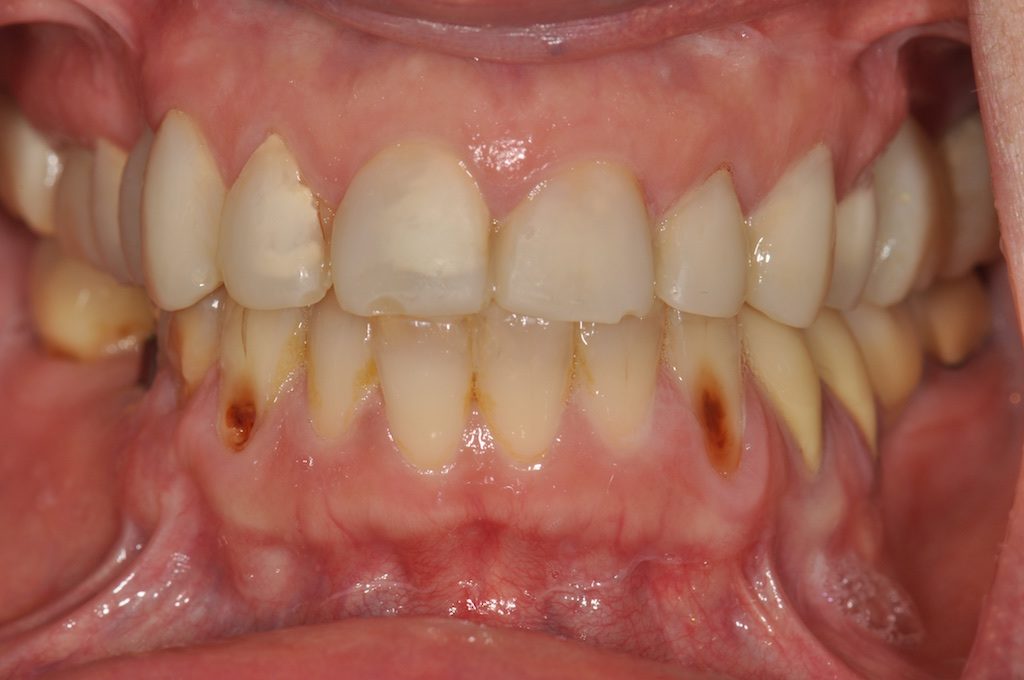

Le cas présenté est celui d’une femme âgée de 61 ans qui, consciente de la dégradation de sa santé dentaire, recherche une prise en charge restauratrice et conjointement une amélioration esthétique de son sourire.

Fig. 2a à 2f : vues intra-buccales de la situation initiale

Analyse dentaire :

• les dents 14, 25, 26, 36 et 46 ont toutes été extraites pour des raisons de délabrements des tissus dentaires (et non pas pour des raisons parodontales),

• les dents 17 et 16 sont dévitalisées et porteuses de coiffes céramo-métalliques dont les limites vestibulaires sont exposées. La dent 36 est remplacée par un bridge céramo-métallique de 4 éléments en appui sur les dents 34, 35 et 37 (dévitalisées),

• les dents 11, 22, 27, 44, 45 et 47 présentent des obturations coronaires en composite qui présentent des signes d’infiltration,

• toutes les les autres dents présentent des signes d’érosion avancée avec des plages d’exposition dentinaires, larges par endroit, vestibulaires, linguales et/ou occlusales.

Analyse parodontale :

On ne note pas de signes – ni cliniques, ni radiologiques – de maladie parodontale (pas de poches, pas de mobilités…).

Le biotype parodontal est fin. On note des récessions gingivales sur les dents et dont certaines sont très proches de la ligne de jonction muco-gingivale. L’alignement des collets des incisives maxillaires est asymétrique.